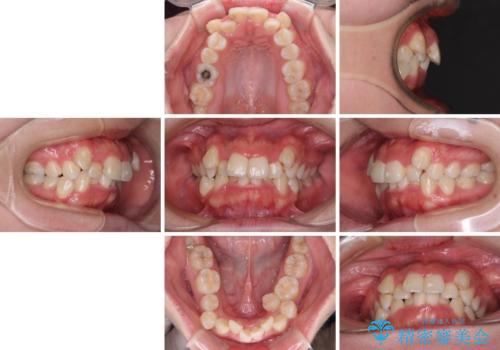

【モニター】八重歯を抜歯矯正でスッキリした口元に

- 20代女性

- 治療期間

- 1年7ヶ月

- 上下の八重歯やデコボコを気にして来院された患者様です。

上下ともに八重歯が顕著であったので、上下左右第一小臼歯4本を抜歯し、補助装置を使用して速やかに改善しながら、ワイヤー装置にて矯正治療を行うこととしました。

気になっていた八重歯は装置装着から3か月ほどで解消されました。

2年以内を目標として治療を開始しましたが、1年半ほどで終えることができました。